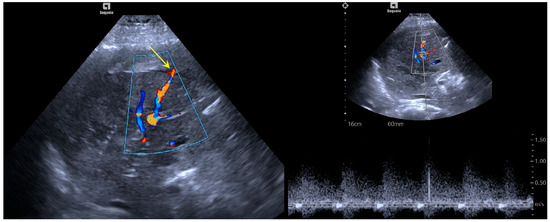

3.2. Treatment Effect